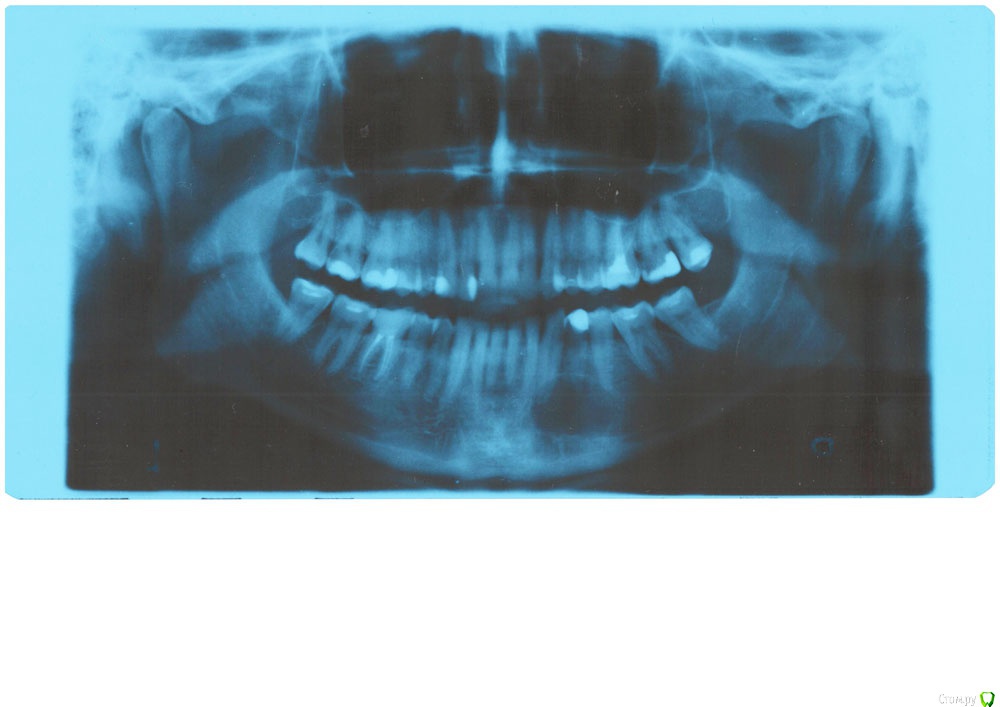

sewif Опубликовано 26 октября, 2019 Поделиться Опубликовано 26 октября, 2019 (изменено) Здравствуйте Есть киста на нижней челюсти в районе клыков. Был на приеме в частной клинике и в городской стоматологии. Оба хирурга сказали одно и тоже:1) Депульпировать два зуба над кистой2) Провести цистэктомию с резекцией верхушки корней двух зубов После поиска информации в интернете по этим манипуляциям (в т.ч. отзывы людей которым удаляли кисту зуба), сложилось впечатление что это обычные/заурядные манипуляции которые можно сделать в каждой второй частной клинике за пару дней. Напрягает следующее: оба хирурга сказали с сомнением в голосе примерно так: " делать нужно эти манипуляции, но не уверен что их можно сделать в условиях нашей клиники. Врач частной клиники (также он работает в Моники) сделал расчет стоимости (~90 тыс. за обе манипуляции), но сказал сходить в городскую поликлинику - возможно на госпитализацию отправят. Врач городской поликлиники сказал, что даст направление на консультацию в Моники. Отсюда мой вопрос, у меня такая запущенная и (или) сложная проблема что оба врача не хотят за нее браться? Во вложении пантомограмма зубов. КТ: https://yadi.sk/d/Zyla-MtONgSG0wФайл: DCMFileType.19 (.dcm) Изменено 26 октября, 2019 пользователем sewif Ссылка на комментарий

krokomot Опубликовано 26 октября, 2019 Поделиться Опубликовано 26 октября, 2019 У вас и на верхней челюсти тоже огромное кистозное образование. 1. определяется витальность зубов, корни которых вовлечены в очаг2. проводится лечение каналов неживых зубов3.дальнейшие действия зависят от симтоматики с хирургическим вмешательством и без. Ссылка на комментарий

сирена Опубликовано 26 октября, 2019 Поделиться Опубликовано 26 октября, 2019 Киста довольно большая,я думаю,надо ложиться в стационар.Сначала на консультацию,конечно. Ссылка на комментарий

сирена Опубликовано 26 октября, 2019 Поделиться Опубликовано 26 октября, 2019 В стационаре чаще оперируют такие кисты(опыта больше),да и по оптг не совсем понятно:это от зуба киста или изолированное поражение челюсти.Там обязательно возьмут материал на гистологическое исследование. Ссылка на комментарий